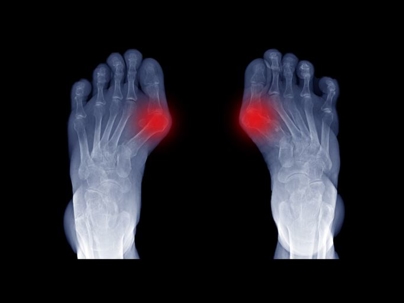

Foot Xray of Big Toe Arthritis

The Cartiva implant is used to relieve arthritis pain in the big toe. The procedure for installing the implant is relatively simple, making it a more appealing option than traditional methods, such as fusion. Unfortunately, some patients have reported only short-term or no relief after getting Cartiva implant surgery. Various explanations exist as to why the device has failed. Yet, there have been no conclusive findings concerning the trouble with the device. Still, the high failure rate has caused some doctors to stop recommending or using the Cartiva implant. Patients adversely affected by the implant may have grounds to file a defective medical device claim.

The Cartiva implant is one option for treating osteoarthritis (or hallux rigidus) in the big toe. The condition results from repetitive stress. Over time, the cartilage is damaged, causing friction between the bones at the joint.

Made from a polyvinyl synthetic, the Cartiva implant is one option for relieving pain resulting from osteoarthritis. The material is pliable and acts as a cartilage replacement. A surgeon makes a hole at the metatarsal head into which the device is inserted. It sits just above the surface of the bone, preventing the joint bones from directly rubbing together.